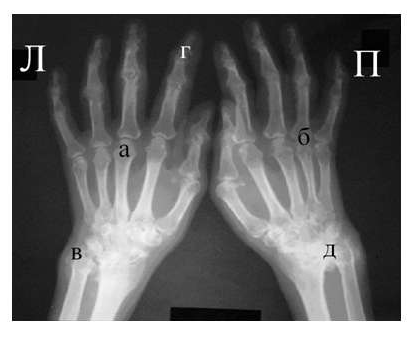

Рис. 3 Сочетание ревматоидного артрита и остеоартроза

Большинство ошибок встречаются при начальных стадиях, особенно при начале РА в пожилом возрасте и сочетании его с остеоартрозом (см. рис. 3). В этом случае для подтверждения диагноза РА и предупреждению случаев его гипердиагностики служит выявление симметричных эрозий в типичных для ревматоидного артрита суставах (запястья, плюснефаланговые, пястно-фаланговые).

Рис. 4. Изменения кистей при ревматоидном артрите (а остеопороз, бсужение суставных щелей, в кистовидные просветвления, г костные эрозии, д анкилозирование)

Необходимо также помнить, что, как правило, при РА эрозии не предшествуют околосуставному остеопорозу, кистам и сужению суставных щелей. Имеет место последовательность развития стадий РА (см. рис. 4), в отличие от эрозивных артритов другого генеза (псориатического, серонегативного)